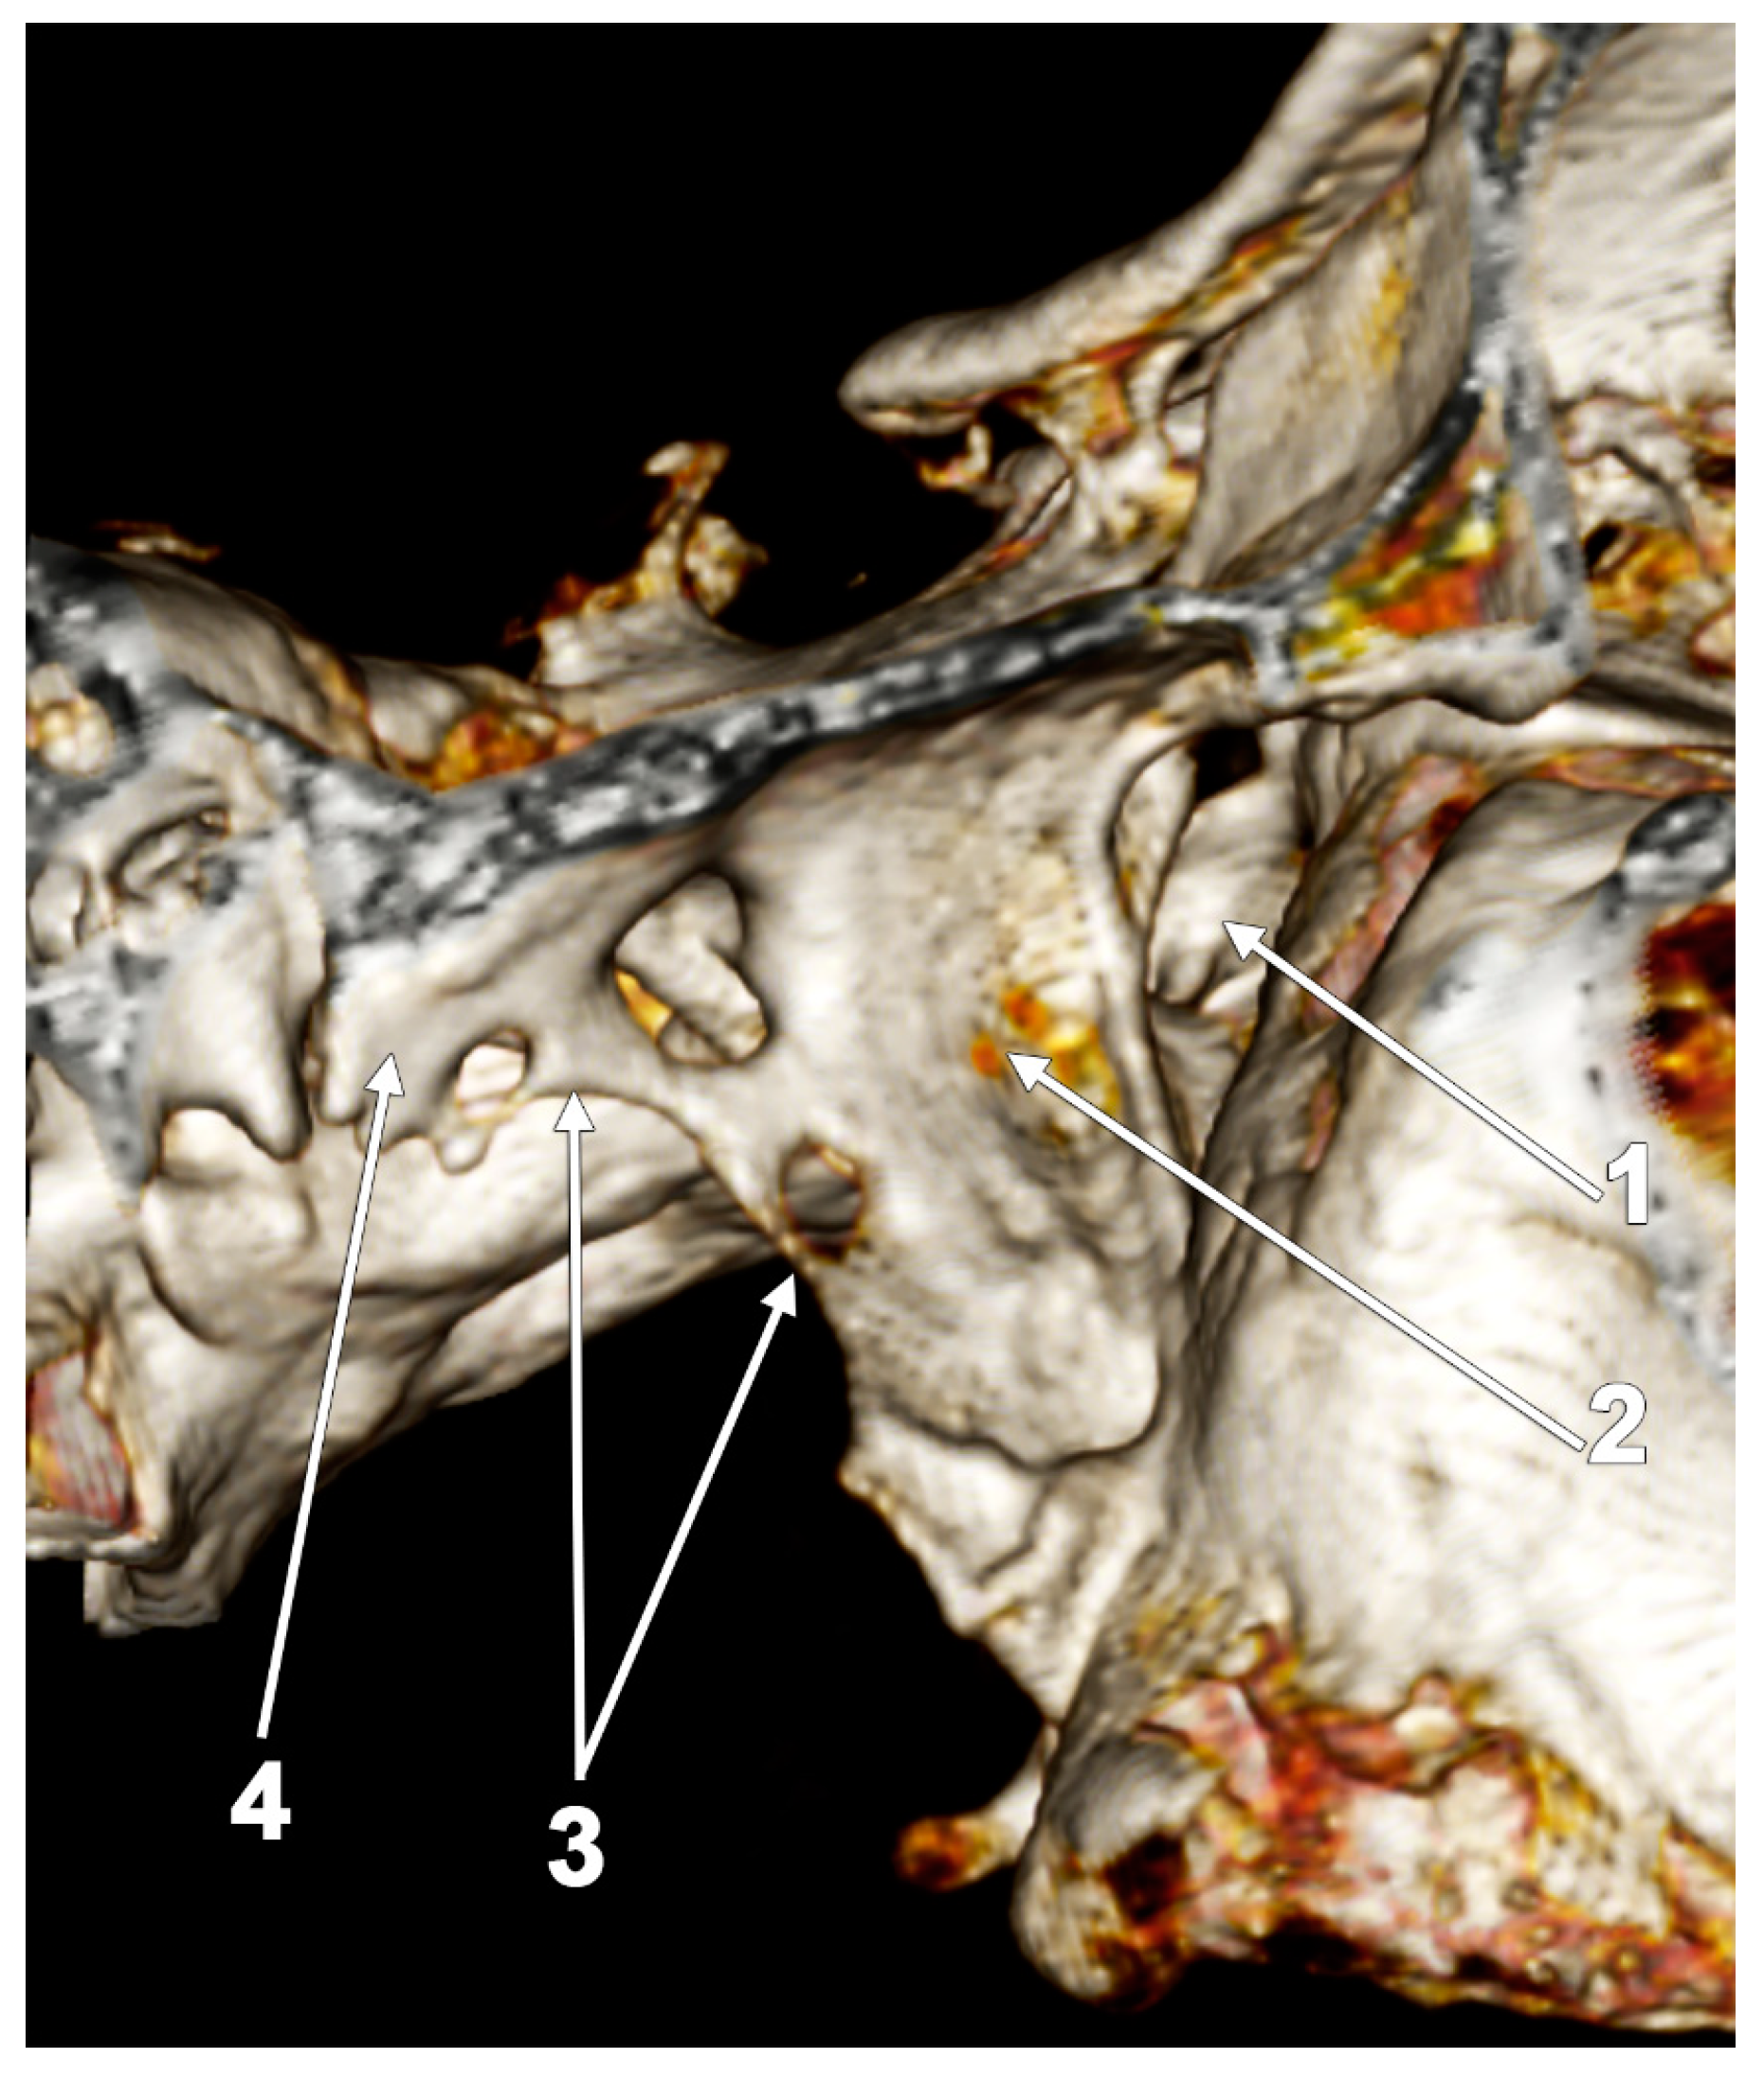

5.1. Broad Lateral Pterygoid Plates

5.2. The Pterygospinous and Pterygoalar Bars